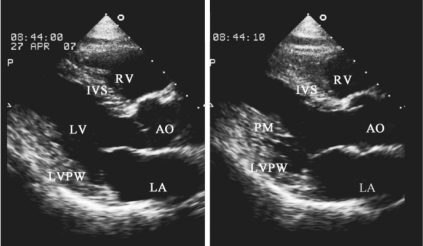

1.14.2.2二、常用切面图及用途

-